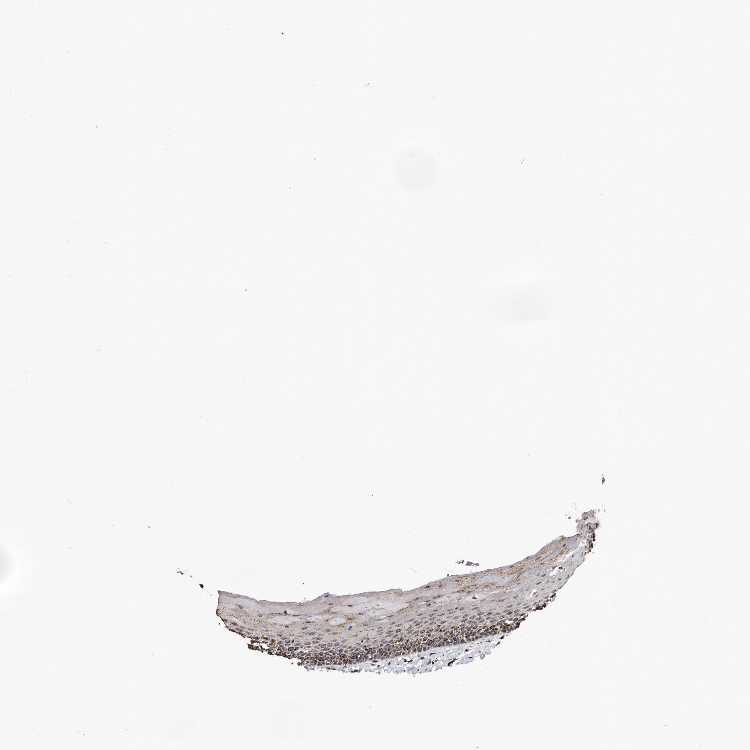

ORAL MUCOSA - Antibody stainingi

Antibody staining in the annotated cell types in the current human tissue is reported as not detected, low, medium, or high, based on conventional immunohistochemistry profiling in selected tissues. This score is based on the combination of the staining intensity and fraction of stained cells.

Each image is clickable and will lead to virtual microscopy that enables deeper exploration of all samples and also displays staining intensity scores, fraction scores and subcellular localization as well as patient and tissue information for each sample.

Antibody HPA030148

Squamous epithelial cells High